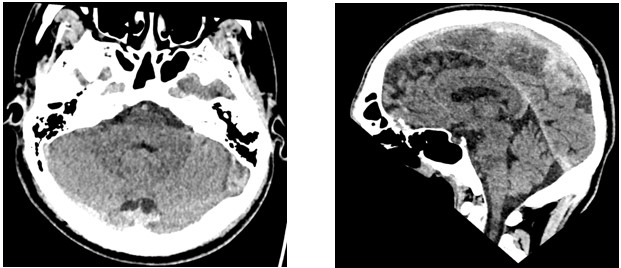

| Figure 2: CT Head Images |

An initial full blood count, serum electrolytes, liver function tests and blood gases were normal. 1g IV paracetamol, ondansetron 4mg IV and NaCl 0.9% was administered via a cannula, with oral codeine 30 mg subsequently once vomiting had subsided. A CT head scan revealed small volume hypertense collection of blood at the left posterior vertex, in keeping with SAH. No mass lesions or midline shift was seen, and there was no evidence of overlying fracture. There was no hydrocephalus or acute infarct, and imaged orbits were normal. Paranasal sinuses and mastoid air cells were aerated with no calvarial fracture.